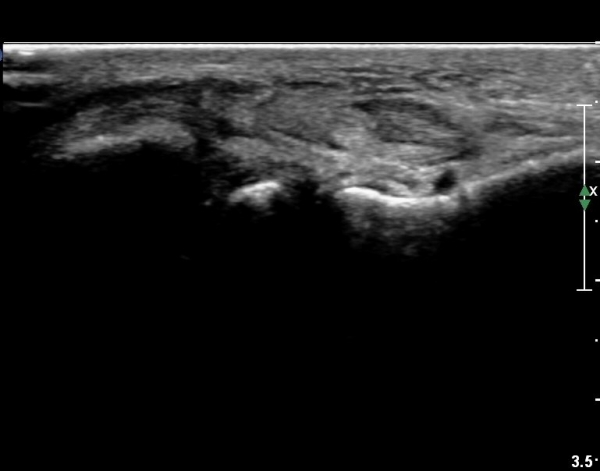

¹ß¸ñ ¾ÕÂÊ Á¾´Ü¸é°Ë»ç¿¡¼­ °üÀý³» ºÎÁ¾À» º¸ÀδÙ(»çÁø 1).

°üÀý³» ºÎÁ¾Àº ½É°¢ÇÑ ¼Õ»óÀ» ¾Ï½ÃÇÏ´Â ¼Ò°ßÀÌ´Ù.

Àü°ÅºñÀδë Á¾´Ü¸é°Ë»ç¿¡¼­ Àü°ÅºñÀδëÀÇ ÆÄ¿­ÀÌ °üÂûµÈ´Ù(»çÁø 4, 5).